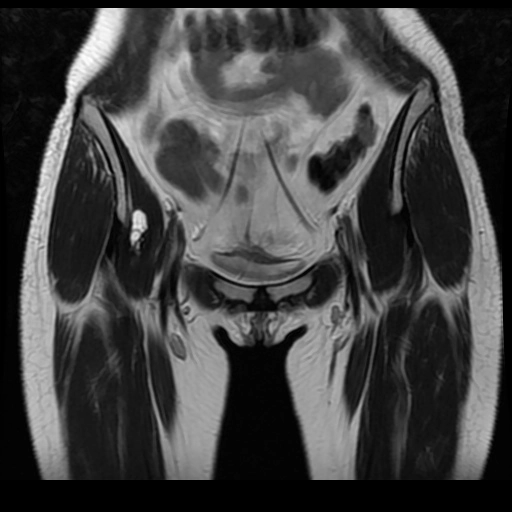

Hoại tử vô mạch chỏm xương đùi (Osteonecrosis of the femoral head)